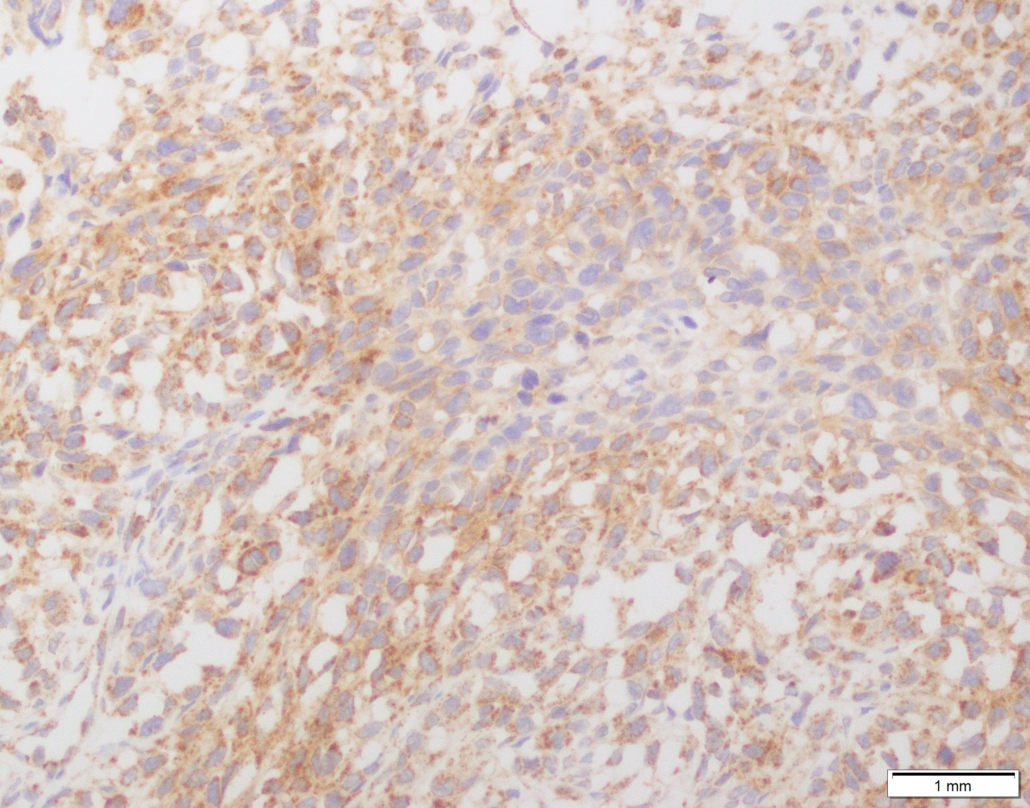

Case 03

Case presented by Dr Shaarif Bashir, FCPS (PAK), Shaukat Khanum Memorial Cancer Hospital and Reserach Centre, Pakistan